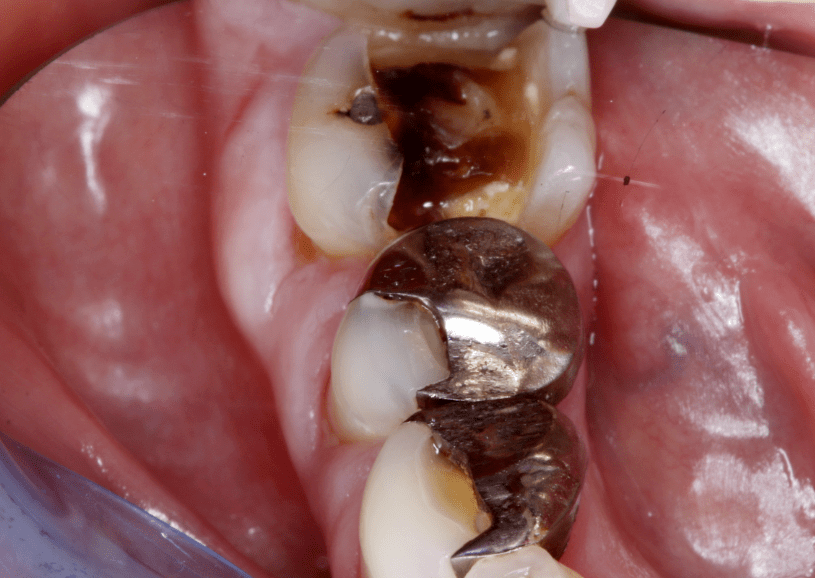

Az amalgámtömések eltávolítása után a fogakat előkészítjük, és lenyomatot veszünk róluk, hogy a fogtechnika ez alapján el tudja készíteni a betétet. A betét színét a páciens saját fogai színéhez igazítjuk. A páciens ideiglenes tömést kap, hogy a végleges betét beragasztásáig komfortosan érezze magát. Fontos, hogy az ideiglenes tömések nem bírják annyira a strapát, mint a véglegesek, ezért az erőteljes rágást ezeken a fogakon a kezelés végééig kerülni kell.

Amalgamtömések eltávolítása utáni előkészítés